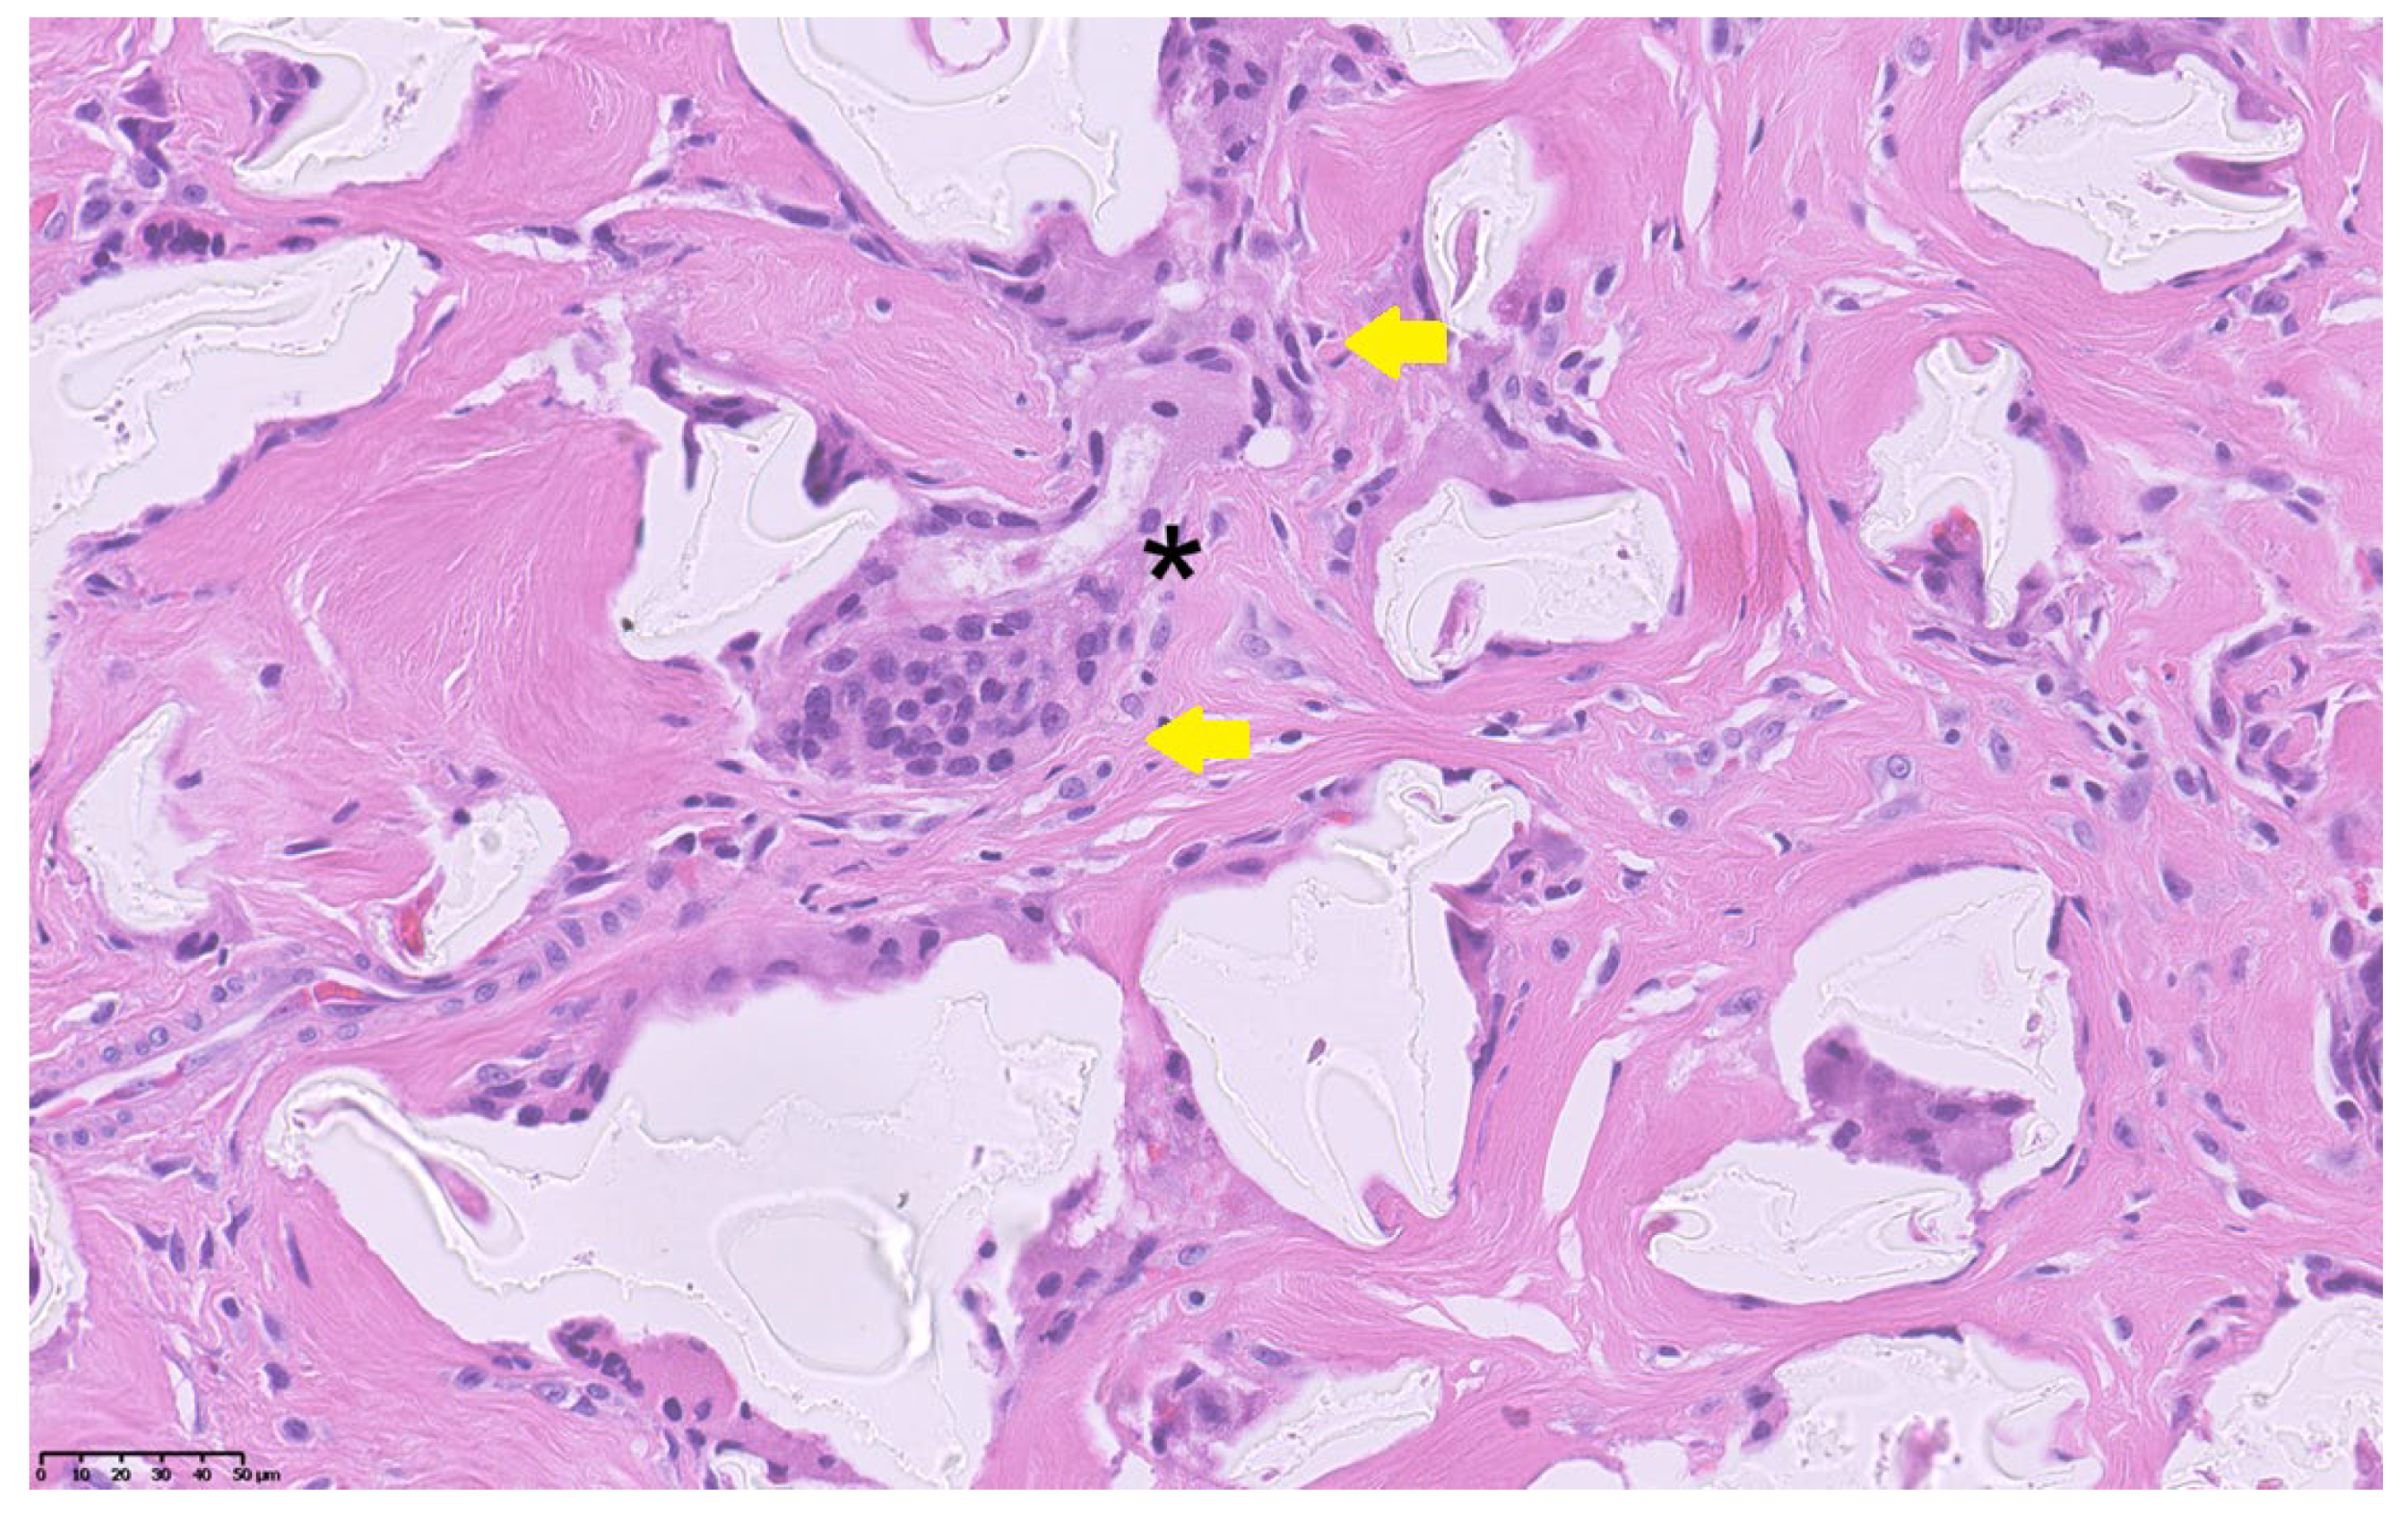

At surgery, a wide fibrotic reaction was present involving the distal ureters, inter-ureteric band, bladder trigone, and anterior division of the pelvic neurovascular bundle. Both the ureters were carefully dissected to achieve sufficient length and reimplanted longitudinally according to the Politano–Leadbetter technique, after resection of the distal tract. Posterior urethra and bladder neck were calibrated until 26 F, thus excluding any organic stenosis. Limited reductive cystoplasty with fundus invagination was finally performed and a suprapubic catheter was positioned. The pathology report of the excised tissue showed a granulomatous reaction with a predominance of foreign-body giant cells, confirming that the massive fibrotic reaction was caused by the presence of non-resorbable Macroplastique® particles (Figure 3).

Figure 3.

Histopathological section showing foreign-body giant cells (yellow arrows) surrounding amorphous non-resorbable material (asterisk) within a dense fibrotic stroma (H&E stain, 40×). Scale bar = 50 µm.

Our patient developed bilateral obstructive megaureter several years after Macroplastique® implantation. The histopathological finding of a foreign-body granulomatous reaction confirmed that the fibrotic process and distal ureteral obstruction were secondary to the persistence of non-resorbable polydimethylsiloxane particles. While the occurrence of late ureteral obstruction and fibrosis after Macroplastique® injection has been largely documented in the literature [5,6,7,8,9], the present case is unique because this complication occurred in a patient with pre-existing urinary tract malformations, thereby complicating both the diagnostic interpretation and the therapeutic approach. The novelty and clinical relevance of the present case does not consist of demonstrating a new causal/eziological link between VACTERL syndrome and Macroplastique®-related fibrosis/obstruction, but in documenting how a known late complication of a non-resorbable bulking agent can become diagnostically and therapeutically far more complex when it occurs in a syndromic patient with VACTERL, who already has congenital urinary tract anomalies and multiple prior reconstructions.

The histological finding of a granulomatous foreign-body reaction involving the trigonal region and periureteral tissues provides a plausible mechanism linking chronic inflammatory fibrosis with both ureteral obstruction and detrusor underactivity. In this context, the involvement of the anterior neurovascular bundle observed intraoperatively may have contributed to the secondary bladder hypocontractility. Although a direct causal relationship between VACTERL syndrome and the bulking agent complication cannot be demonstrated, the main educational message of this report is that patients with VACTERL often have pre-existing urinary tract malformations and altered pelvic anatomy due to multiple early reconstructions, and therefore a higher chance that a late iatrogenic event presents atypically and is diagnosed late.